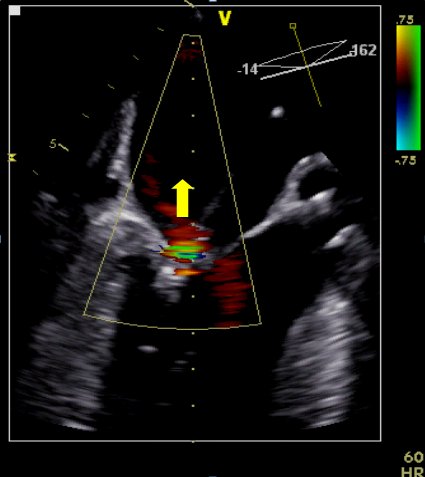

Auf den Bildern sehen Sie eine Echokardiografie vor (01), während (02) und nach (03) einer kathetergestützten Rekonstruktion der Mitralklappe mittels MitraClip®. Der große Pfeil zeigt eine ausgeprägte Undichtigkeit vor dem Eingriff (01). Der rote Kreis markiert die MitraClip-Implantation (02). Und der kleiner Pfeil verdeutlicht eine nur noch geringe Undichtigkeit nach dem Eingriff (03).